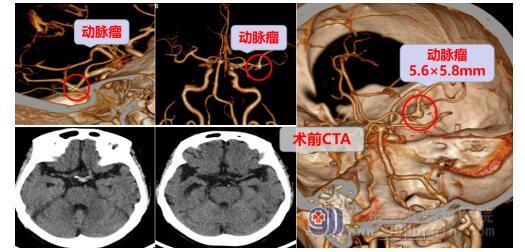

患者入院后经过CTA检查,竟然发现了熊阿姨除一般的脑血管狭窄外,还有一个“大脑中动脉分叉处动脉瘤”。动脉瘤可是颅内的“不定时炸弹”,如果破裂(爆炸)则会有生命危险。神经外十科主任欧阳辉教授召集科室团队制定了一套手术方案,在全麻下行右侧大脑中动脉分叉部动脉瘤夹闭术+硬脑膜修补术+颅骨成形术,术中生命体征平稳,术后恢复顺利。